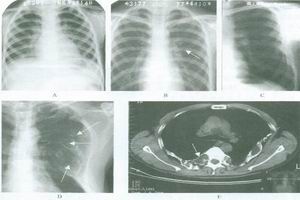

1.X線檢查MAS的骨組織被異常增生的纖維組織所取代,表現為不同程度的骨膨脹,骨皮質變薄,但完整。骨密度可為均勻性減低,或呈磨玻璃樣,或見條索狀、斑點緻密陰影。國內總結X線分4型:

(1)囊狀改變:分單囊和多囊,邊緣硬化,囊內常見條狀骨及斑點狀緻密影,常見於管狀骨和肋骨。

(2)毛玻璃改變:髓腔囊狀膨脹呈毛玻璃狀密度,內可有條狀骨紋和斑點狀鈣化。

(3)絲瓜筋狀改變:骨小梁粗大扭曲,頗似絲瓜筋狀,嚴重者如蛛網狀,長管狀骨粗大,骨狀紋一般和縱軸平行。

(4)蟲蝕狀改變:單發或多發的溶骨性改變,邊緣銳利如蟲蝕樣,可類似溶骨性轉移性破壞。

此外,脊柱和長骨常伴病理性骨折。